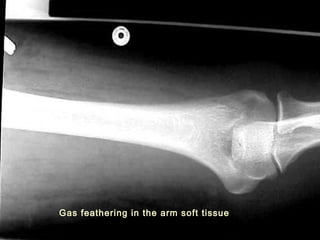

IMAGING STUDIES

Radiograph –

 Delineate the typical feathering pattern of gas in

soft tissue

 Gas may not be present in patients

 Gas in soft tissue does not confirm diagnosis

Gas feathering in the arm soft tissue